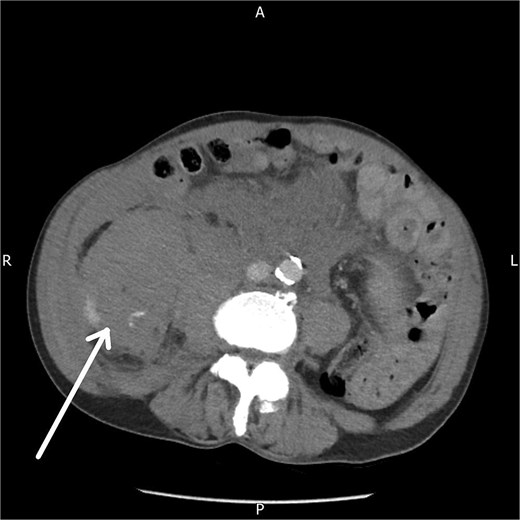

A contrast-enhanced CT abdomen and pelvis performed five hours after presentation demonstrated a large right-sided retroperitoneal haematoma extending from the perinephric region into the psoas compartment, with clear evidence of active arterial extravasation (Fig. 1). Splenic enlargement with patchy enhancement was also noted, felt to represent a perfusion abnormality. No underlying mass or vascular lesion was identified.

Axial contrast-enhanced CT abdomen and pelvis demonstrating a right-sided retroperitoneal haematoma with evidence of active contrast extravasation.